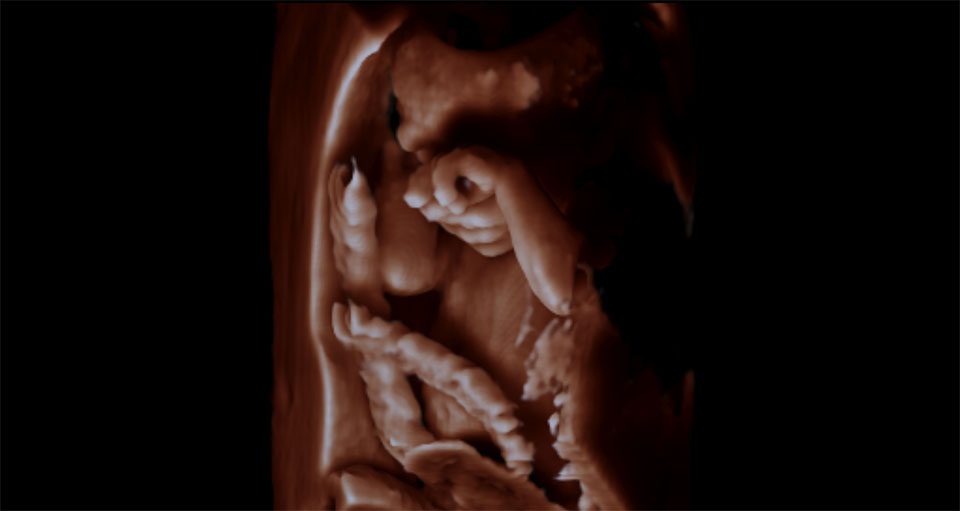

3D-4D ultrasound of a fetus imaged with a GE Volusion E10 system. It shows the yoke sac.

Below is a collection of prenatal ultrasound pictures from the Imaging Technology News (ITN) archive. Use the arrows to click through the image gallery. It includes transvaginal ultrasound images and fetal echocardiogram images. Fetal imaging is referred to by many names, including pregnancy sonograms, pregnancy ultrasound, endovaginal ultrasound, obstetric ultrasound, OB ultrasound, baby ultrasound, prenatal ultrasound. Fetal heart ultrasound is also called baby echo or prenatal echo.